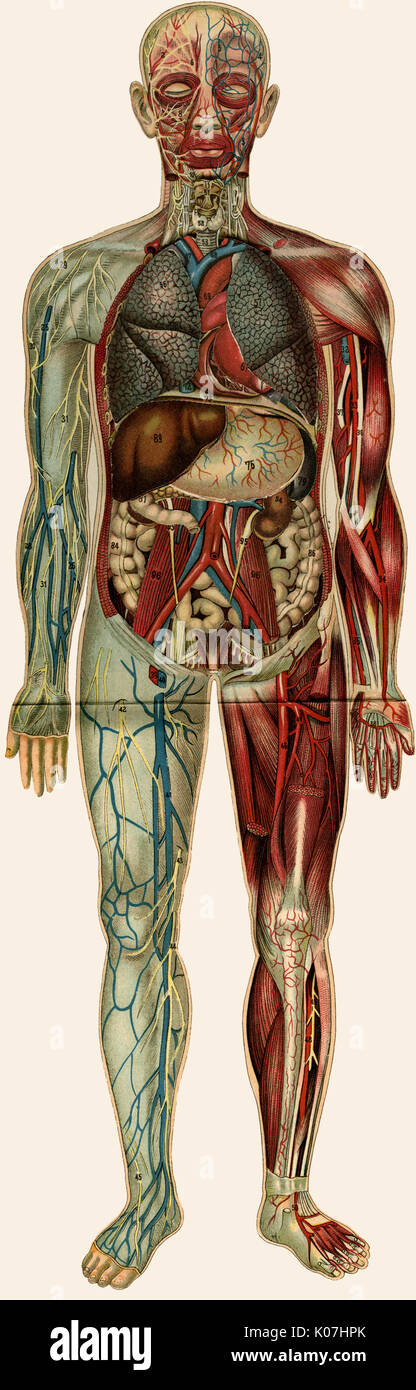

RFPAYTH0–Innere Organe, männlichen Körper - schematische Darstellung der menschlichen Anatomie Illustration - auf weißem Hintergrund.

RFDGYRD7–Männliche Anatomie, inneren Organe allein, volle Atmungs- und Verdauungssystem, mit einigen Organen Cutaway. Anatomie-Bild.